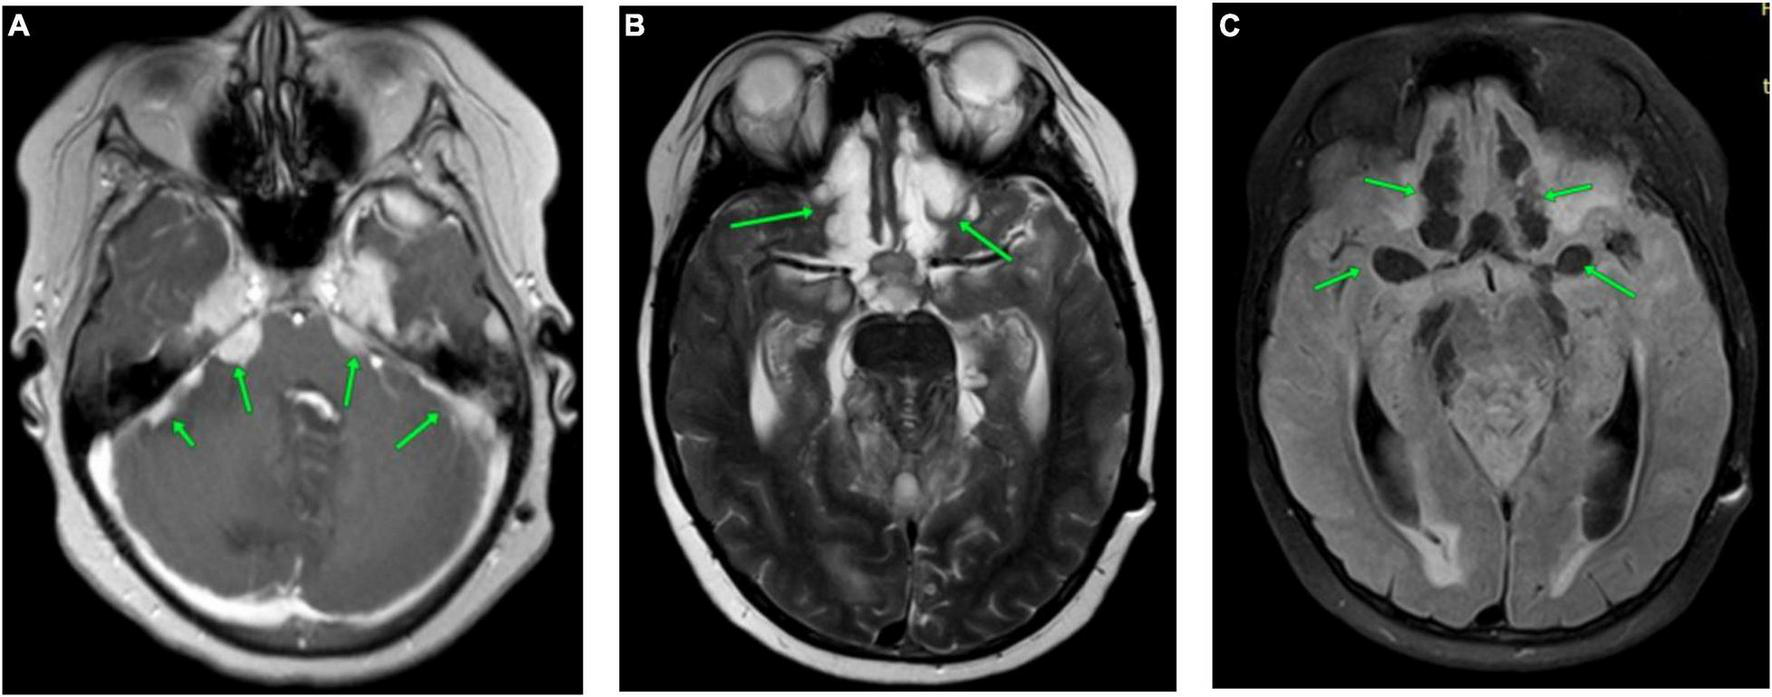

The subsequent MRI examinations revealed an increased size of nodular thickenings of dura mater in the area of the tentorium cerebelli (Figure 2A and Supplementary Figures 5A,B); increased cerebral edema in the area of frontal lobes, in the poles of the temporal lobes and cerebellar hemispheres; persisted and progressed diffuse infiltrative changes in the meninges; and increased zones of cystic transformation of the medulla in the cerebellum and frontal lobes (Figures 2B,C and Supplementary Figure 6). Due to the impairment of the patient’s status and negative dynamics of neuroimaging data, a biopsy of the pathological region of the cerebellar pia mater was performed (6 months after the clinical manifestation of the disease).

FIGURE 2

CNS MRI of the patient after 5.5 months of the debut of the disease. (A) Brain MRI (post-contrast CE T1-WI). Accumulation of contrast agent by thickened meninges in cerebellar tentorium (green arrows). (B) Brain MRI (T2-WI). (C) Brain MRI (TIRM). Significant increase in cystic lesions of the frontal lobes (green arrows).